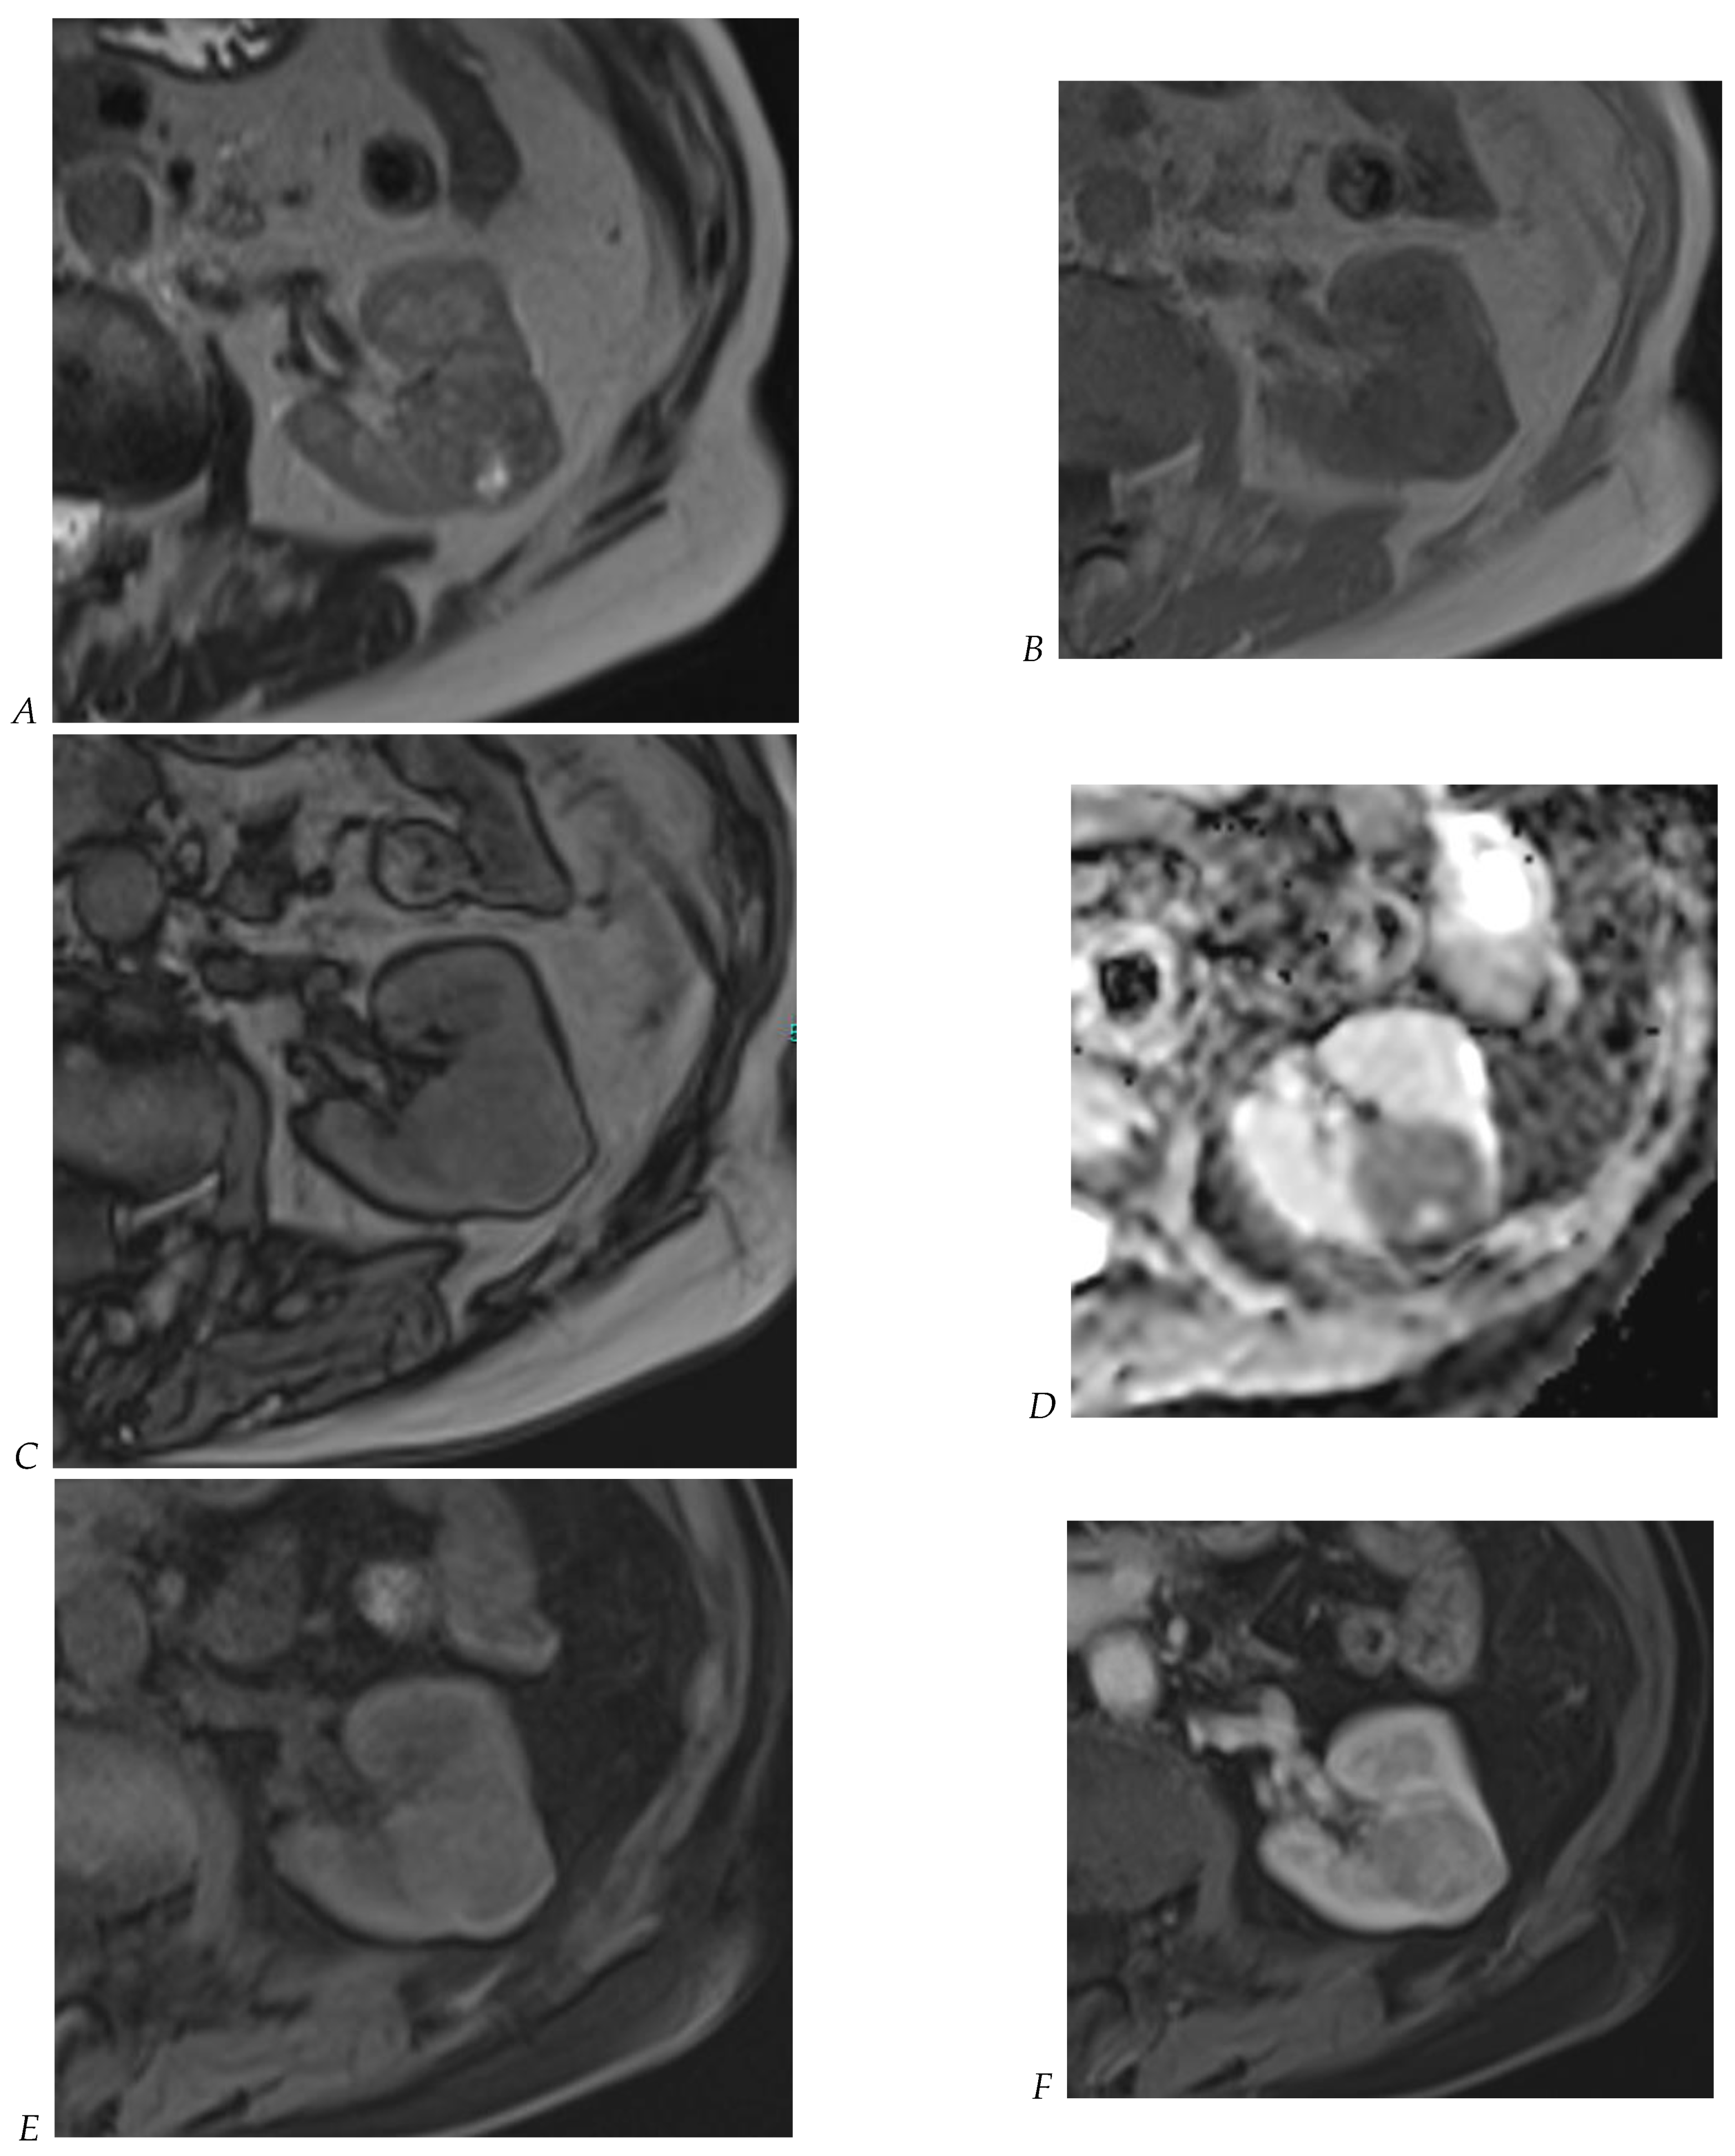

Figure 9.

Same lesion as Figure 2. Oncocytoma in the right kidney of a 42-year-old man. (A) The axial T2-weighted fast SE image shows a heterogeneous lesion with a central hyperintense area. Transverse in-phase (B,C) opposed-phase MR images show no significant loss of signal intensity on the opposed-phase image. (D) The lesion is hyperintense on the diffusion-weighted image. Transverse nonenhanced (E) and gadolinium-enhanced T1-weighted gradient-echo spoiled MR images in (F) corticomedullary, (G) nephrographic, (H) and delayed phase images show early enhancement and rapid washout.